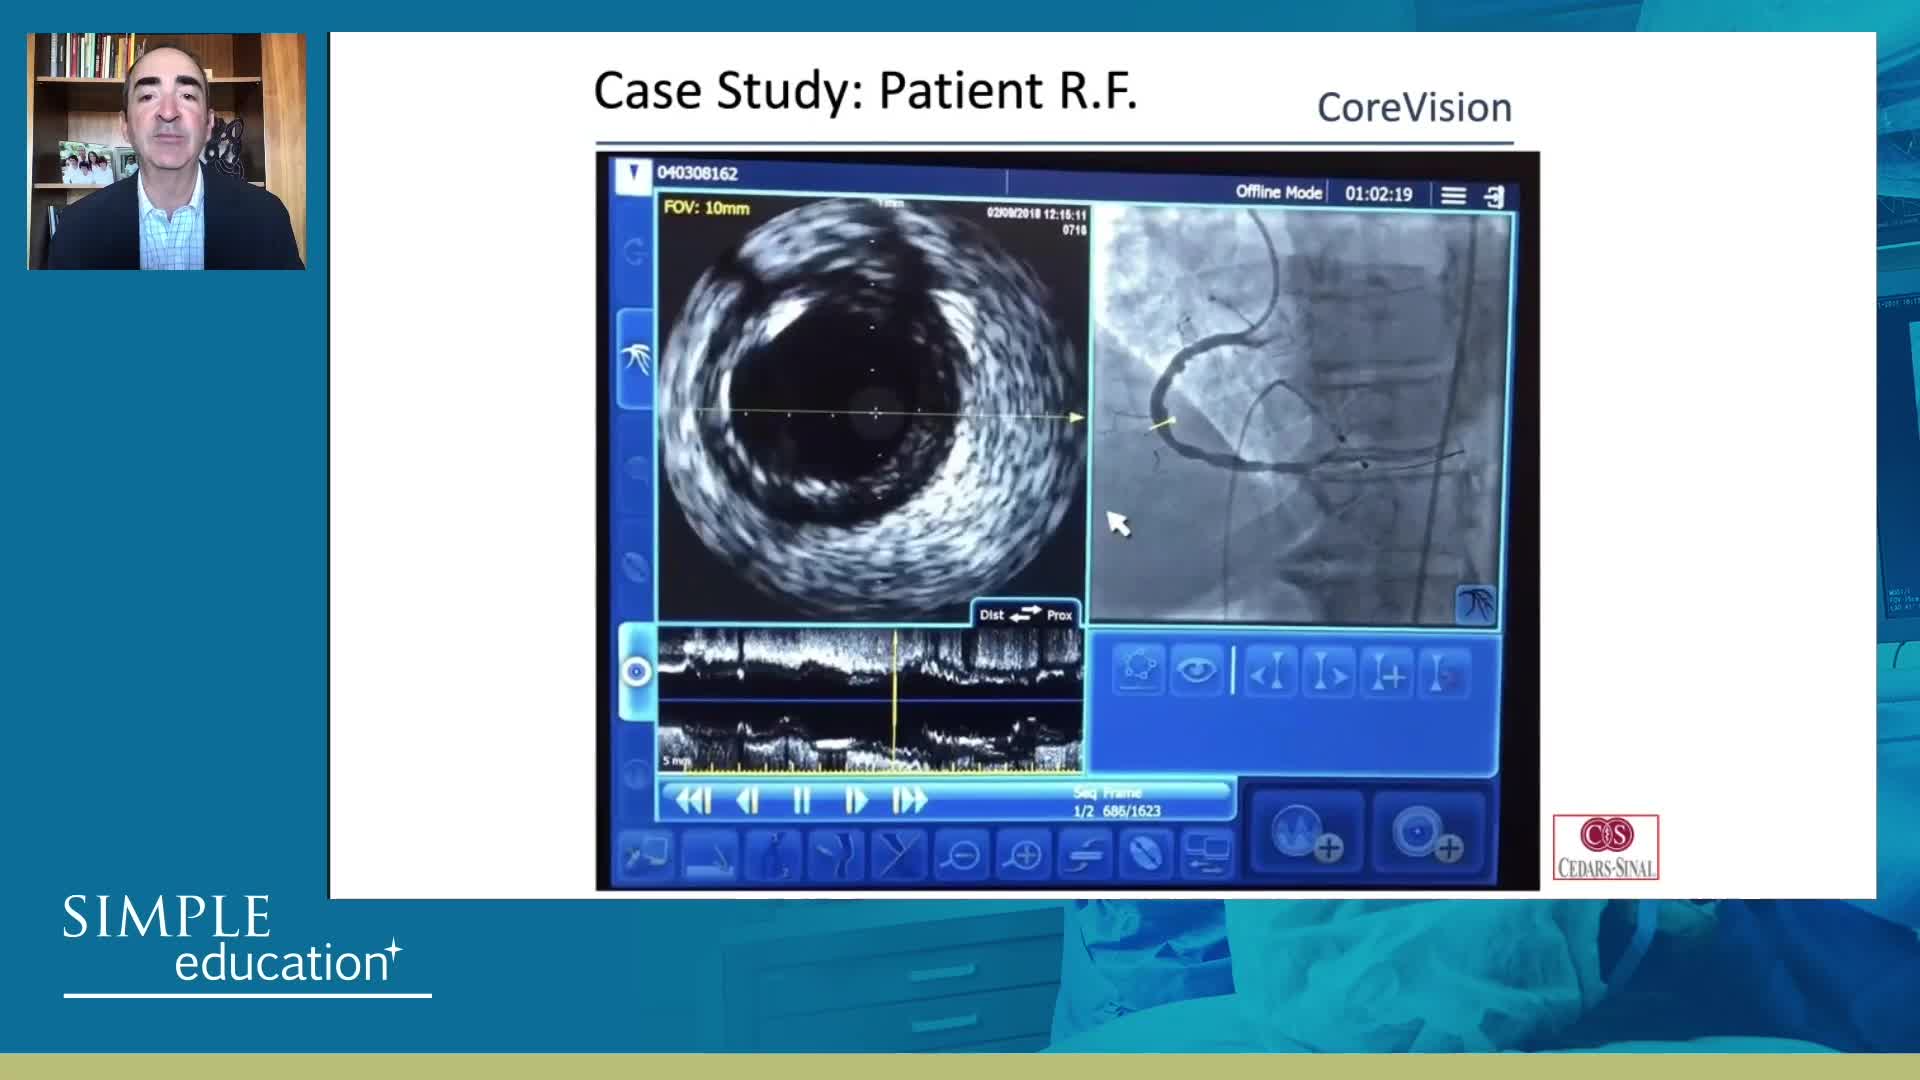

How to perform good co-registration measurements using iFR and IVUS - Prof Carlo Di Mario

Using SyncVision Co-registration to distinguish between focal and diffuse coronary disease. - Prof Giuseppe Tarantini

Essential steps for physiology-based PCI planning and guidance - Dr Allen Jeremias

Intracoronary guidance in acute coronary syndromes - Dr Hernan Mejia-Renteria